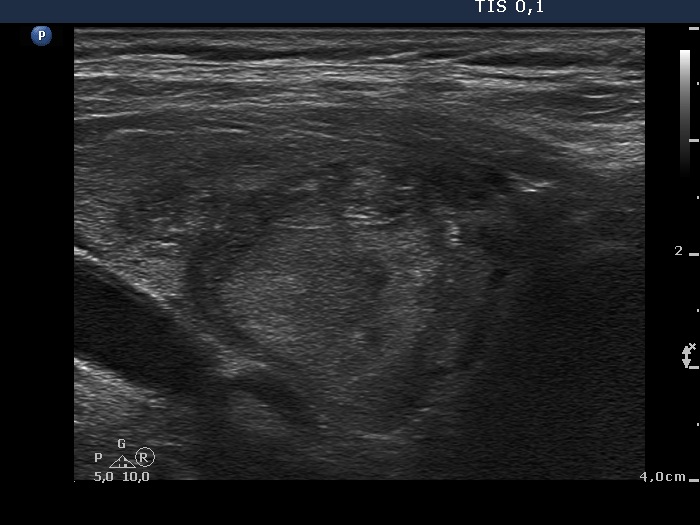

Ultrasonography. The thyroid was minimally hypoechogenic and had multiple discrete lesions which were mostly echonormal. The thyroid had a pseudonodular pattern. There were several hypoechogenic discrete areas.

Cytology from a hypoechogenic lesion in the lower pole of the left lobe resulted in benign colloid goiter.